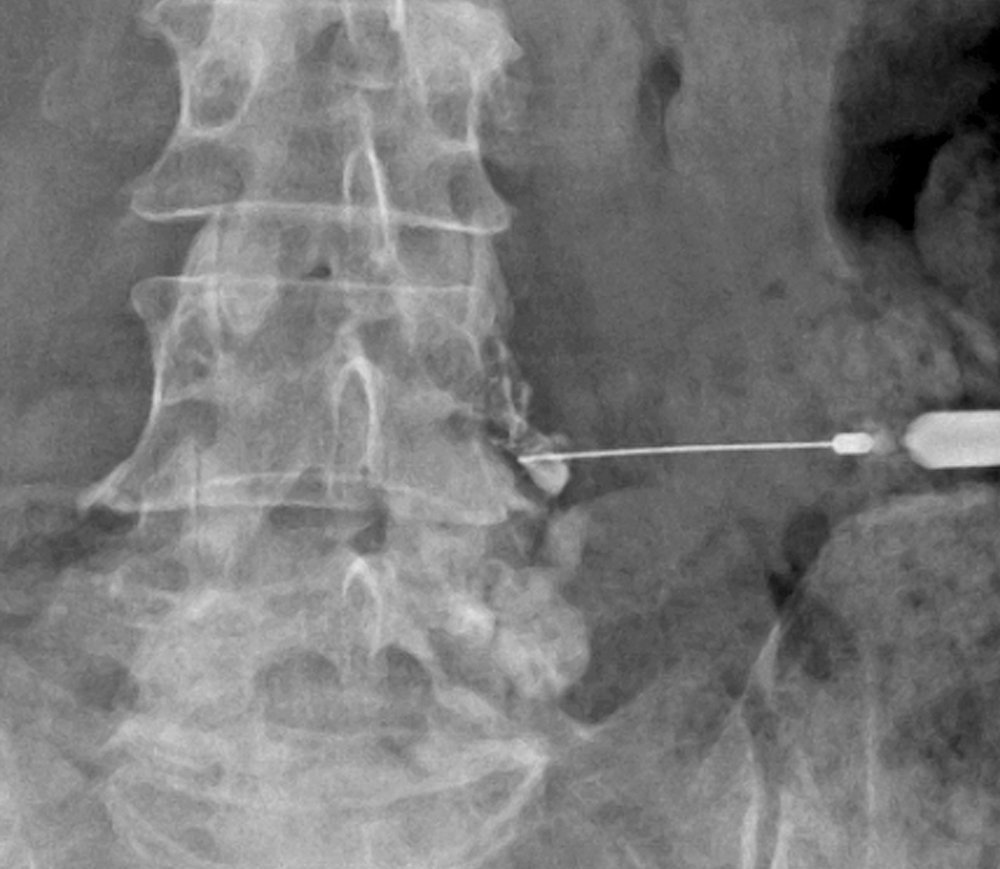

척추 신경주사치료는 통증을 유발하는 척추 신경 주변에 직접 약물을 주입하여 염증을 가라앉히고, 과민해진 신경을 안정시켜 통증을 완화하는 정밀한 시술입니다. 실시간 영상 장치(C-arm)를 보면서 병변 부위를 정확하게 확인하고 치료하므로 안전하고 효과가 빠릅니다.

특정 척추 신경 뿌리(신경근)가 눌려 통증이 발생할 때, 영상 장치로 보면서 해당 신경에 직접 약물을 주입하는 방법입니다.

4. C-arm 주사 삽입과 약물주입